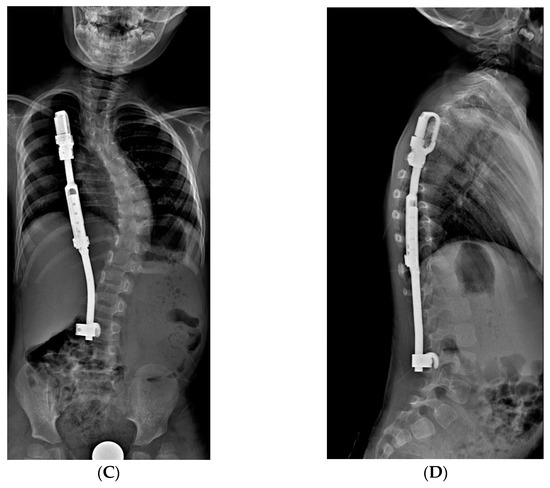

2.3.2. MCGR: Magnetically Controlled Growing Rods